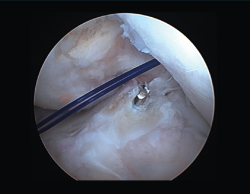

La posición del túnel femoral ha sido la que más cambios ha experimentado en las últimas décadas. Las primeras plastias con técnica monotúnel (con un túnel femoral prácticamente vertical) ofrecían muy buena estabilidad anteroposterior, pero con escaso control de la estabilidad rotacional y frecuentemente con un pivot shift test positivo en el postoperatorio. Las nuevas técnicas tienden a horizontalizar la plastia a través de un portal accesorio anteromedial (Figuras 11A y 11B), dando así mayor estabilidad dual, tanto anteroposterior como rotacional. Este gesto técnico, con la rodilla en posición artroscópica de flexión, puede provocar un túnel femoral excesivamente anterior, con la consecuente pérdida de función estabilizadora de la plastia. Es muy importante hallar la huella anatómica del LCA original. El cambio de portal artroscópico para su correcta visualización es un gesto técnico sencillo y de utilidad (Figura 12).

Figura 12. Visión artroscópica desde el portal anteromedial.